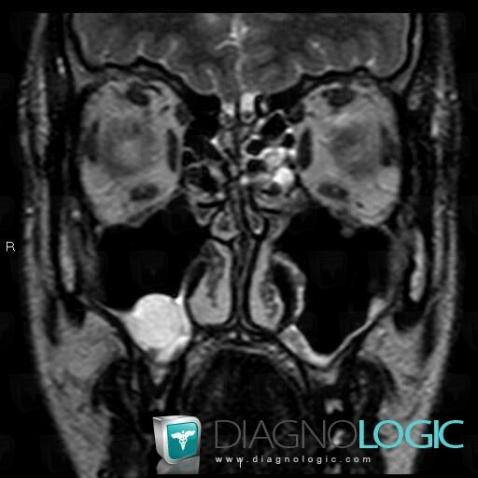

Les images ci-dessous illustrent ce dossier pour les diagnostics Kyste sous muqueux, pour les modalités (IRM)

Les gammes relatives à ce cas sont les suivantes : :

- Masse intra sinusienne

- Masse sinusienne de signal ou densité liquidienne

- Comblement sinusien

Voici les informations spécifiques à l'image clé ci dessus:

- Diagnostic Kyste sous muqueux, Localisation(s) Sinus, comportant les gammes Masse intra sinusienne, Masse sinusienne de signal ou densité liquidienne, Comblement sinusien